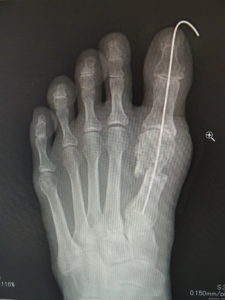

手術前 手術後4年

最近では、原則として固定ワイヤーは経皮的の一本のみとし、ワイヤーの先端は皮膚の外に出ているので、抜く時(術後3週間目)の患者さんの負担はほぼありません。こうすることによるデメリットはなく、むしろ術後成績は良くなっています。

(図6)

手術前 手術後

(図7)

真田理事長による手術の様子。外反母趾|症例 (左から 手術前、手術後、ワイヤ抜去後)